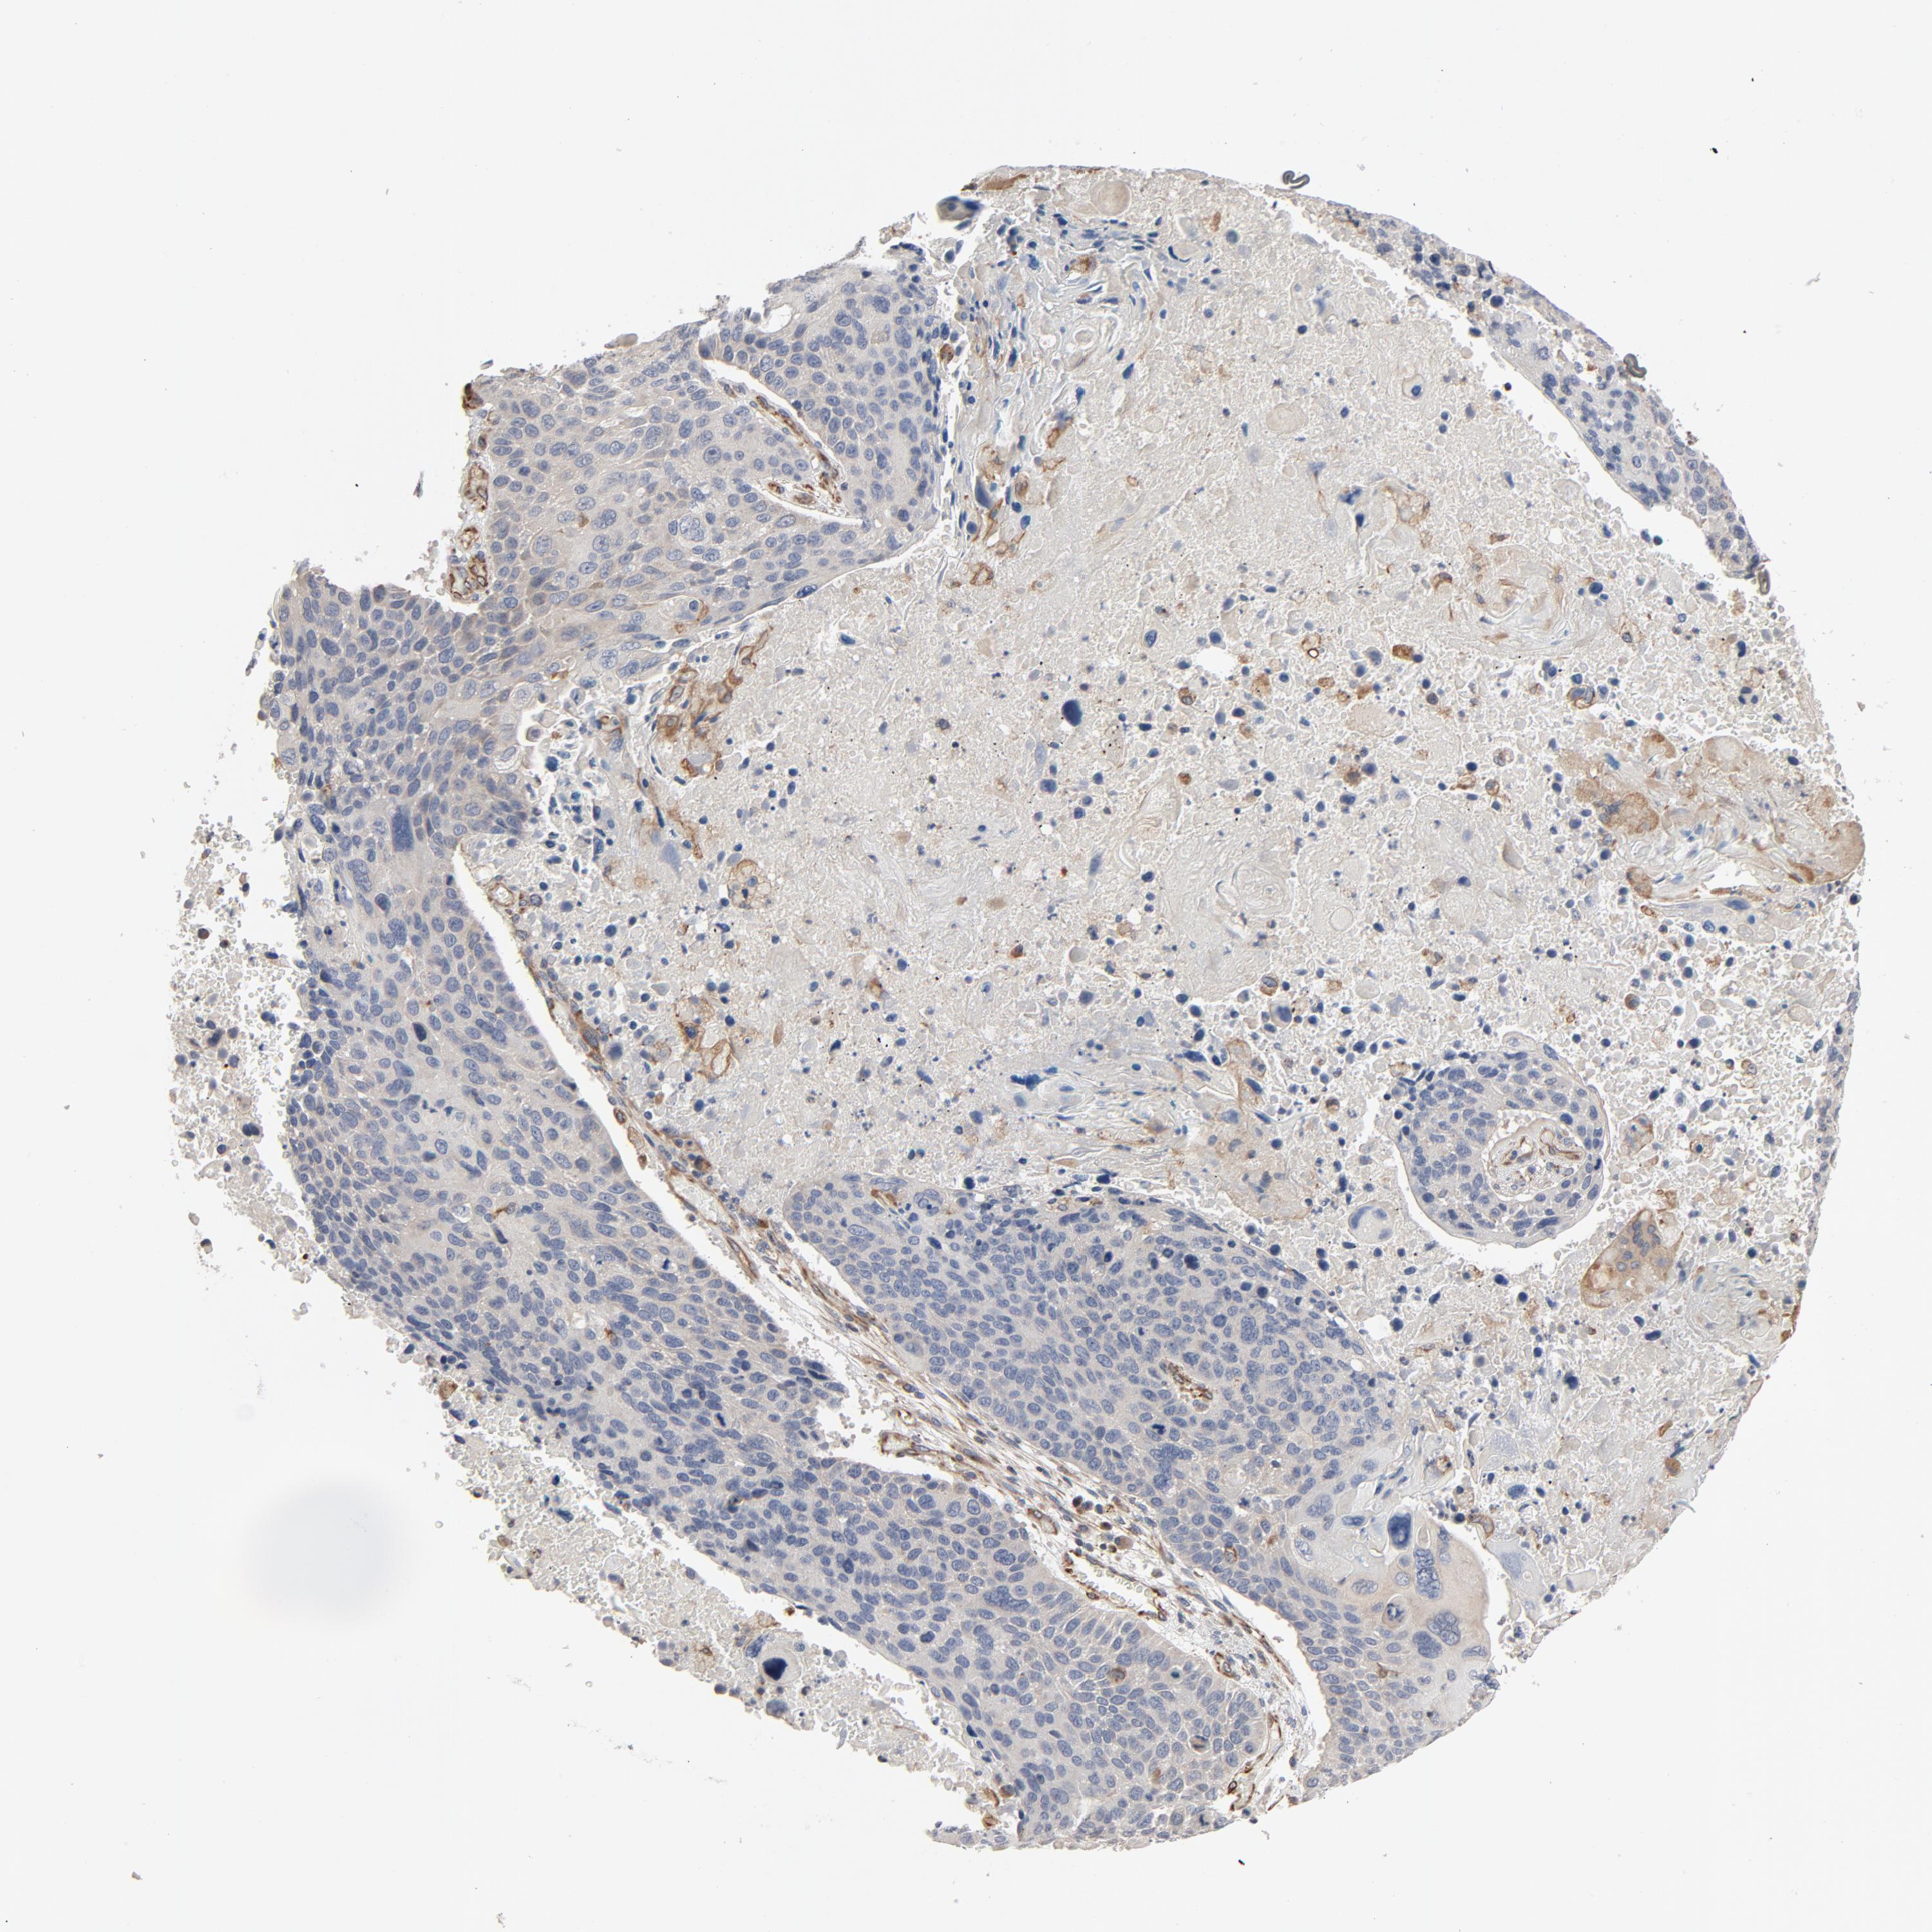

LUNG ADENOCARCINOMA (VALIDATION) - Interactive survival scatter ploti

The Survival Scatter plot shows the clinical status (i.e. dead or alive) for all individuals in the patient cohort, based on the same data that underlies the corresponding Kaplan-Meier plots. Patients that are alive at last time for follow-up are shown in blue and patients who have died during the study are shown in red.

The x-axis shows the expression levels (FPKM) of the investigated gene in the tumor tissue at the time of diagnosis. The y-axis shows the follow-up time after diagnosis (years). Both axes are complimented with kernel density curves demonstrating the data density over the axes. The top density plot shows the expression levels (FPKM) distribution among dead (red) and alive patients (blue). The right density plot shows the data density of the survived years of dead patients with high and low expression levels respectively, stratified using the cutoff indicated by the vertical dashed line through the Survival Scatter plot. This cutoff is automatically defined based on the FPKM cutoff that minimizes the p-score. The cutoff can be changed by dragging the vertical line or by entering a cutoff value in the square labeled "Current cut-off".

Under the Survival Scatter plot the p-score landscape (black curve; left axis) is shown together with dead median separation (red curve; right axis). Dead median separation is the difference in median mRNA expression between patients who have died with high and low expression, respectively. It is calculated as follows: median FPKM expression of dead patients with high expression - median FPKM expression of dead patients with low expression. This is intended to aid the user in visually exploring custom cutoffs and the associated p-scores and dead median separation.

Individual patient data is displayed and can be filtered by clicking on one or more of the category buttons on the top of the page. Categories describing expression level and patient information include: high, low, alive, dead, female, male and tumor stages. The scale of the x-axis can be toggled between linear and log-scale by clicking on the "x log" button. Mouse-over function shows TCGA ID, patient information and mRNA expression (FPKM) for each patient.

& Survival analysisi

Kaplan-Meier plots summarize results from analysis of correlation between mRNA expression level and patient survival. Patients were divided based on level of expression into one of the two groups "low" (under cut off) or "high" (over cut off). X-axis shows time for survival (years) and y-axis shows the probability of survival, where 1.0 corresponds to 100 percent.

TRIOBP is not prognostic in Lung Adenocarcinoma (validation)

Current cut offi

Current cut-off shows the cut-off (FPKM) currently selected. It may be changed manually. When the current cut-off is changed, the vertical dashed line indicating cut-off, the interactive survival scatter plot and the Kaplan-Meier curve will be automatically adjusted to show results accordingly.

:

Best expression cut offi

Based on the FPKM value of each gene, patients were classified into two groups and association between prognosis (survival) and gene expression (FPKM) was examined. The best expression cut-off refers the FPKM value that yields maximal difference with regard to survival between the two groups at the lowest log-rank P-value. Best expression cut-off was selected based on survival analysis .

When clicking on this number, the vertical dashed line indicating cut-off, the interactive survival plot, and the Kaplan-Meier curve will be adjusted to show results based on the best expression cut-off.

: 22.12

Median expressioni

Median expression refers to the median FPKM value calculated based on the gene expression (FPKM) data from all patients in this dataset. When clicking on this number, the vertical dashed line indicating cut-off, the interactive survival plot, and the Kaplan-Meier curve will be adjusted to show results based on the median expression.

: N/A

Median follow up timei

Median follow up time refers to the median time (years) after diagnosis with this type of cancer, based on clinical data from all patients in this dataset.

P scorei

Log-rank P value for Kaplan-Meier plot showing results from analysis of correlation between mRNA expression level and patient survival.

N/A

5-year survival highi

5-year survival for patients with higher expression than the expression cutoff.

For melanoma and glioma, 3-year survival is shown.

5-year survival lowi

5-year survival for patients with lower expression than the expression cutoff.

TCGA RNA samplesi

RNA-seq data is reported as average FPKM (number Fragments Per Kilobase of exon per Million reads), generated by the The Cancer Genome Atlas (TCGA) .

Normal distribution across the dataset is visualized with box plots, shown as median and 25th and 75th percentiles. Points are displayed as outliers if they are above or below 1.5 times the interquartile range. FPKM values of the individual samples are presented next to the box plot.

Average pTPM 19.4

Number of samples 105